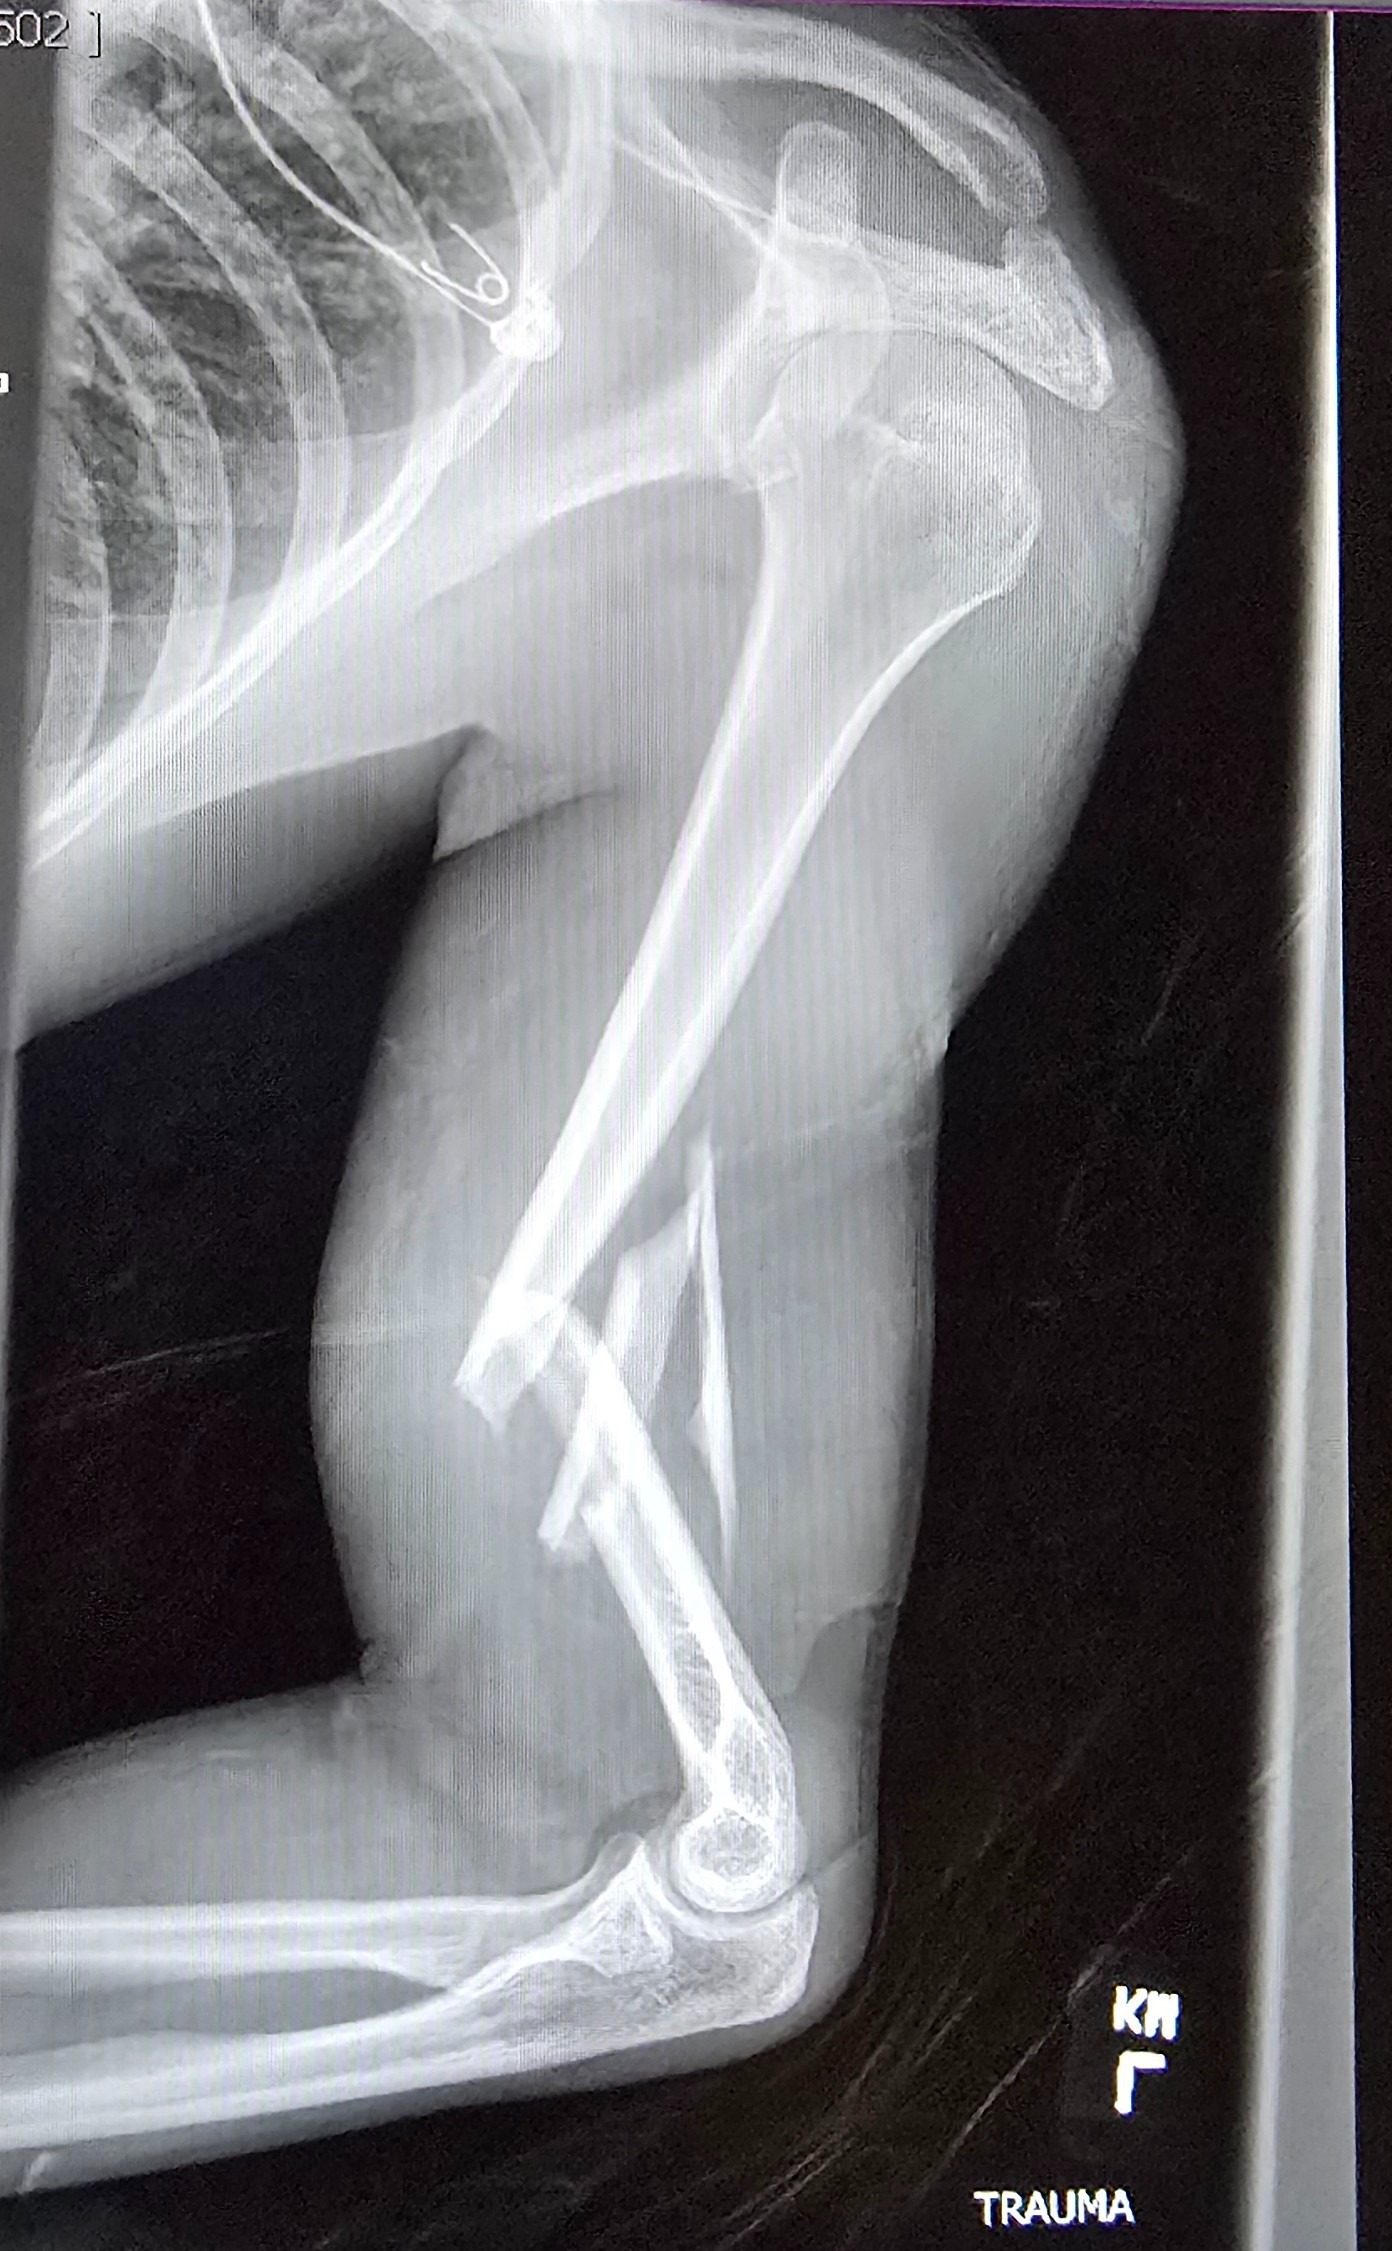

Even though he was wearing his seatbelt, the entire impact hit his left side. His left arm was shattered into multiple pieces, causing severe nerve damage. His left femur was broken into three pieces. He also struck his head against the window.

He was rushed to the hospital, where he spent a long night in unbearable pain before undergoing nearly eight hours of emergency surgery the next morning. Surgeons worked tirelessly to reconstruct his arm and leg. Today, Cole lives with metal rods and screws permanently placed in both his arm and leg.

When he woke up, he couldn’t move his left hand, only slight finger twitches. Doctors still don’t know if he will regain full use of it.